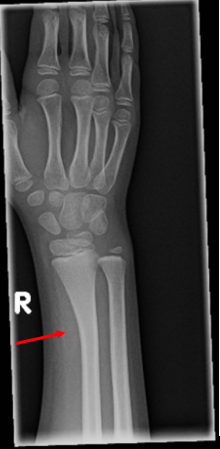

This patient sustained a bowing fracture of the radius. The x-ray shows abnormal gentle bowing of the radial shaft without any definite fracture line or cortical break, as well as soft tissue swelling.

- Bowing fractures of the long bones occur exclusively in children and adolescents

- Radius and ulna are the most common sites, followed by the fibula

- Because they’re softer, more elastic, and have thinner cortex, pediatric bones tend to bend under angulated longitudinal force/stress. With low force, the bones bend and return to normal shape and position upon release of the force. If the force is greater than the mechanical strength of the bone, the bone undergoes a plastic deformation and remains deformed and bowed upon release of the force. Pathologically these bowed bones have multiple micro fractures along the concave border of the bone which are not visible on radiographs